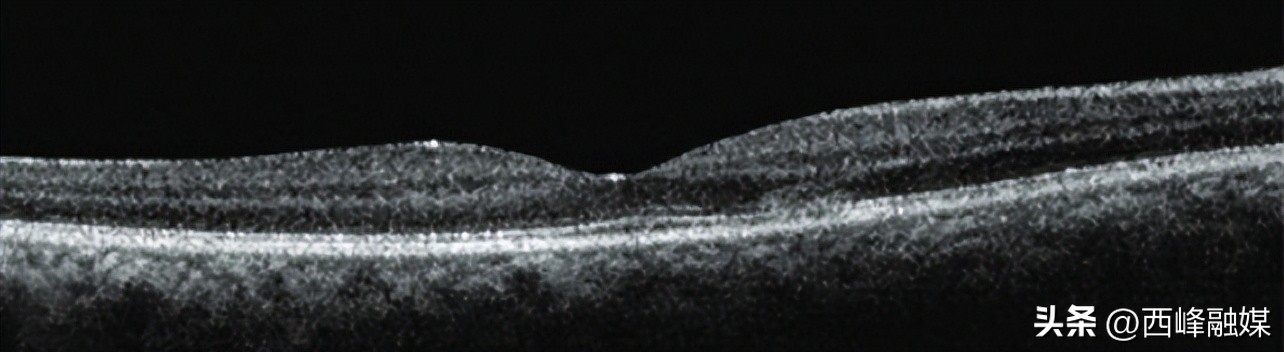

急性黄斑区神经性视网膜病变是一种罕见的疾病,病因不明,但约50%已被证明与呼吸道或流感样疾病有关,有几例确诊新冠肺炎后发生急性黄斑区神经性视网膜病变已经被报道。常见的症状是急性无痛性视力减退、中心旁暗斑和色觉障碍。眼底检查图像病变不明显,OCT检测外丛状层、外核层或外丛状和内核层之间的高反射率结合病史可能帮助诊断。